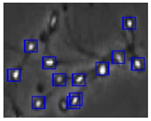

| Case | Conventional Image Processing | YOLOv3-spp | YOLOv5s | YOLOv5s-SA |

|---|---|---|---|---|

| 1 | ![]() | ![]() | ![]() | ![]() |

| 2 | ![]() | ![]() | ![]() | ![]() |